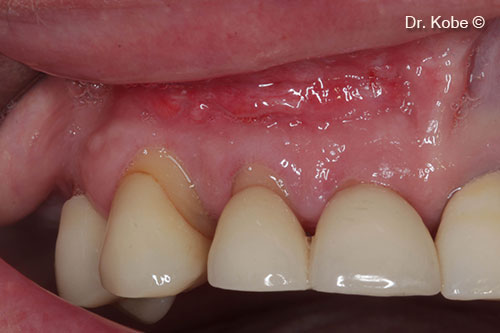

Initial situation

A female patient (55 years old) shows a deep periodontal defect in the upper jaw